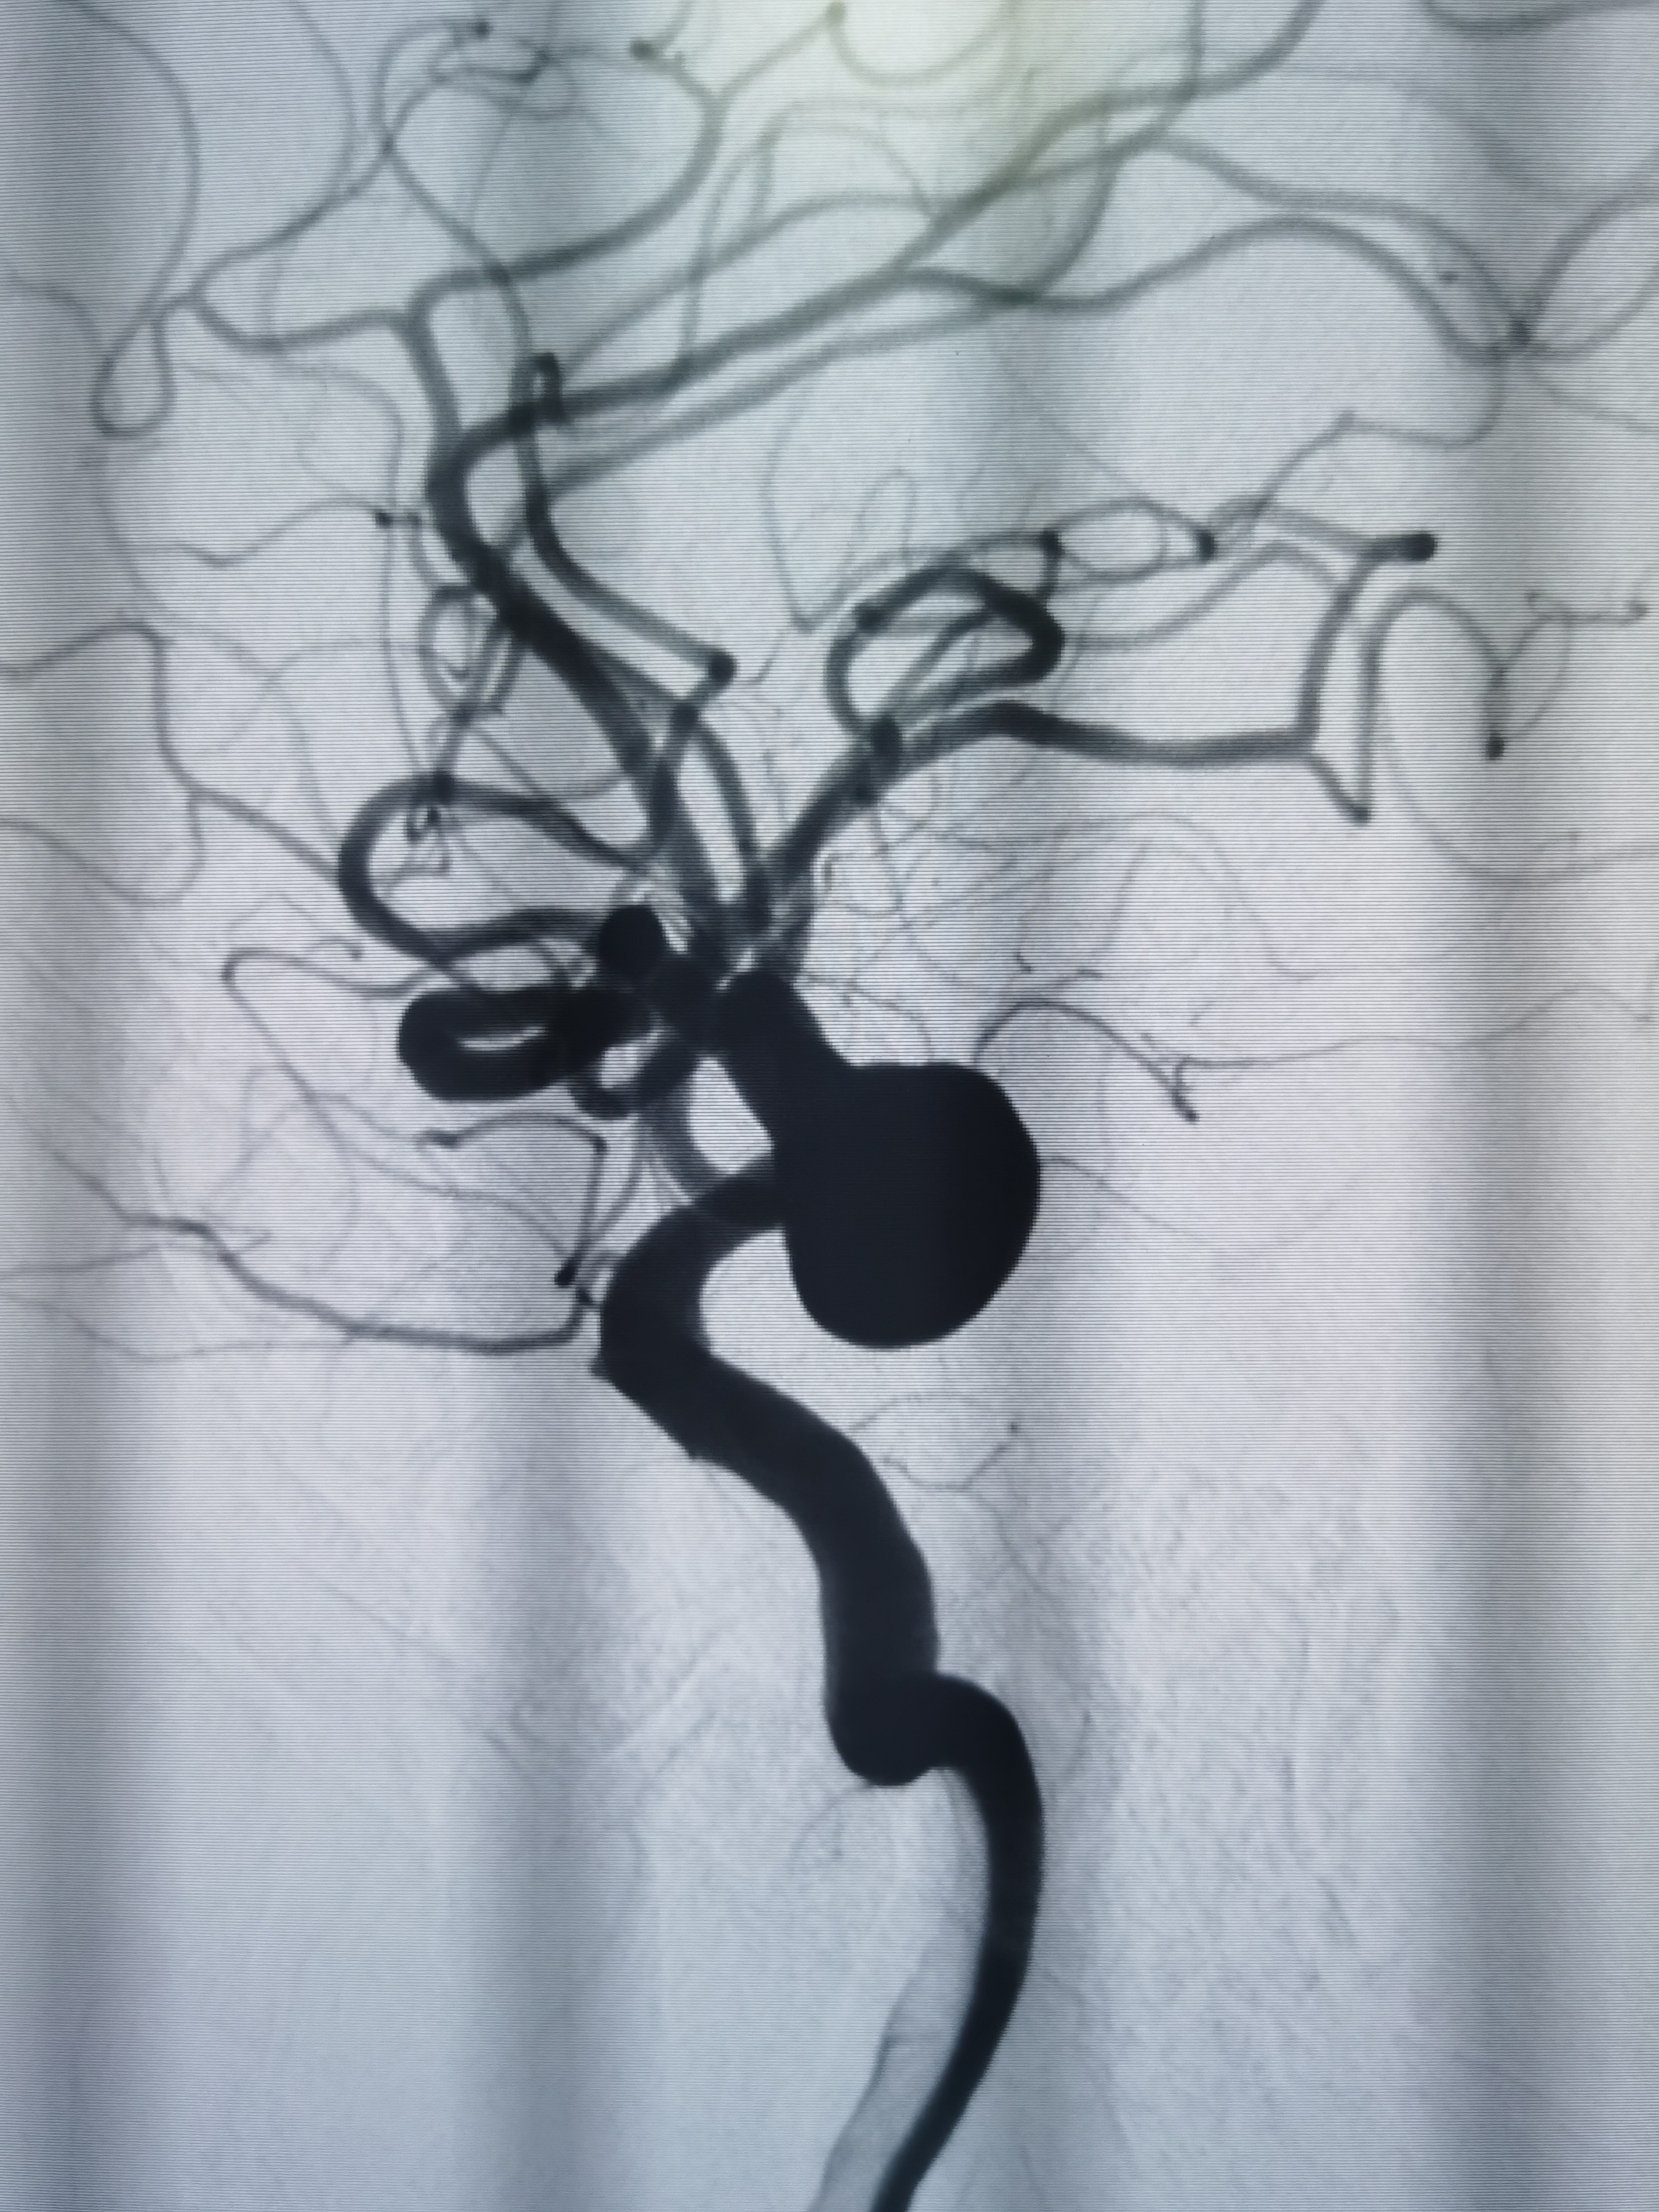

DSA示右侧大脑中动脉M1远端重度狭窄。

左侧颈内动脉C7动脉瘤改变。

术后即刻造影见动脉瘤栓塞较完全。

术后造影见动脉瘤栓塞较为完全,载瘤动脉通畅,遂未再植入支架,逐渐撤出各级导管,缝合股动脉结束手术。